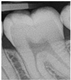

| 0 | Sound![]() | No shadow![]() | No radiolucency![]() |

| 1 Early | First Visual change in enamel![]() | Thin grey shadow into enamel![]() | Radiolucency in outer half of enamel![]() |

| 2 Distinct | Distinct Visual change in enamel ![]() | Wide grey shadow into enamel![]() | Radiolucency in inner half if enamel +/- Enamel dentin junction![]() |

| 3 Distinct | Localized enamel breakdown![]() | Shadow less than 2mm in dentine![]() | Radiolucency limited to outer 1/3 of dentine![]() |

| 4 Distinct | Underlying dentinal shadow![]() | Shadow more than 2 mm in dentine![]() | Radiolucency passed 1/3 of dentine![]() |